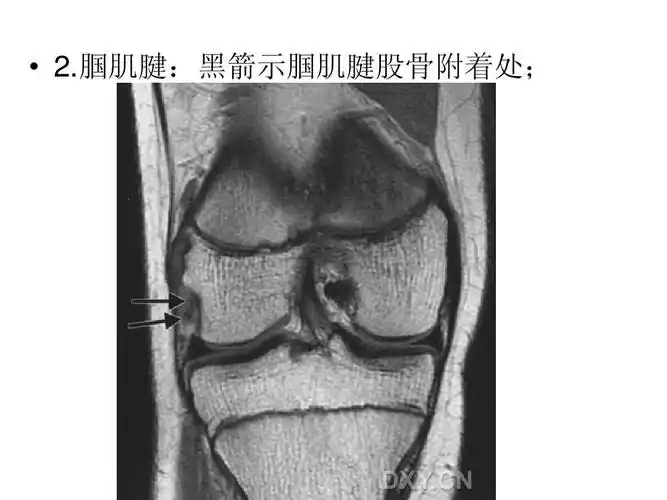

腘肌腱:黑箭示腘肌腱股骨附着处